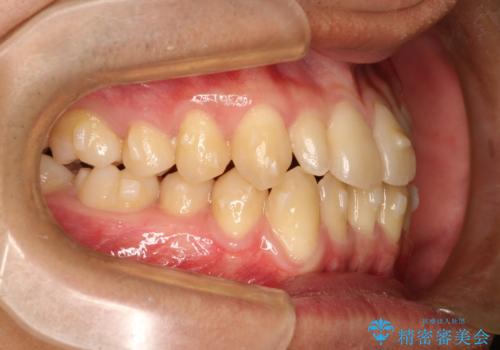

- 前歯のがたつきが気になるとのことで来院されました。

骨格的なところと、上下の歯の大きさのことを考慮して、下の前歯を1本抜歯し、インビザラインにて矯正治療することとなりました。

上の前から2番目の歯がもともと小さかったため、最後にかぶせ物を装着することで、自然な仕上がりにできました。